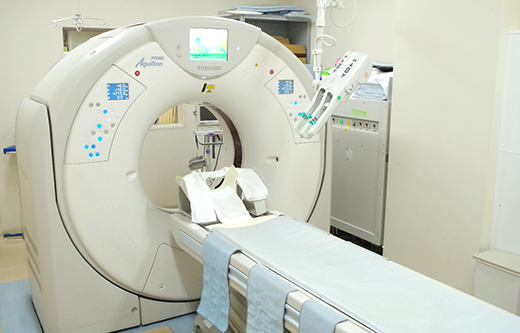

CT

- Canon Aquilion PRIME 80列

頭部から足先まで、全身の輪切りの撮影を短時間で行えます。

また造影剤を使用することにより、全身血管、心臓の撮影も行うことができます。

撮影したデータをコンピューターで処理する事で、多方向からの断面像や3D画像を作成する事ができます。